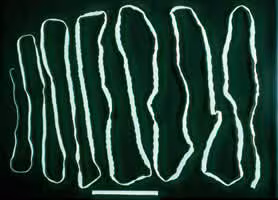

Taenia spp. adults.

. In the human intestine, the cysticercus develops over 2 months into an adult tapeworm, which can survive for years. The adult tapeworms attach to the small intestine by their scolex

and reside in the small intestine

. Length of adult worms is usually 5 m or less for T. saginata (however it may reach up to 25 m) and 2 to 7 m for T. solium. The adults produce proglottids which mature, become gravid, detach from the tapeworm, and migrate to the anus or are passed in the stool (approximately 6 per day). T. saginata adults usually have 1,000 to 2,000 proglottids, while T. solium adults have an average of 1,000 proglottids. The eggs contained in the gravid proglottids are released after the proglottids are passed with the feces. T. saginata may produce up to 100,000 and T. solium may produce 50,000 eggs per proglottid respectively.